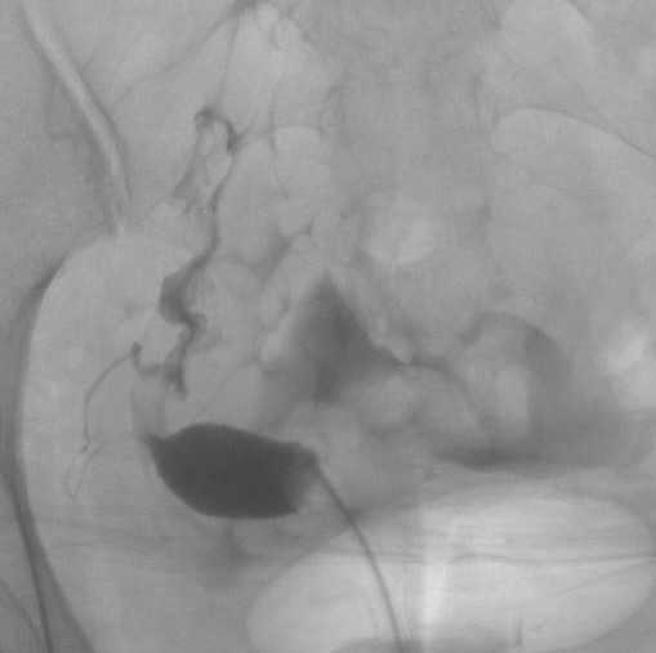

大方公开单角子宫的输卵管摄影照,陈伶宣乐观称自己是「独角兽」。(图/陈伶宣提供)

检查后被判定为单角子宫,陈伶宣解释:「只剩一边的输卵管、卵巢 有功能,一般人能一次能植入两颗胚胎,而我因为子宫空间不足,只能植入一颗。」而TFC臺北妇产科诊所生殖中心医师谭舜仁也表示,「单角子宫子宫血流较差,着床率较低,试管婴儿植入胚胎的深度不好掌握。」一般大约是4000人中才有一个,其中23%单角子宫女性不孕,即便成功怀孕也有34%流产机率,更有10.5%的胎儿可能会不幸胎死腹中,也有20.1%的孕妇最后早产。